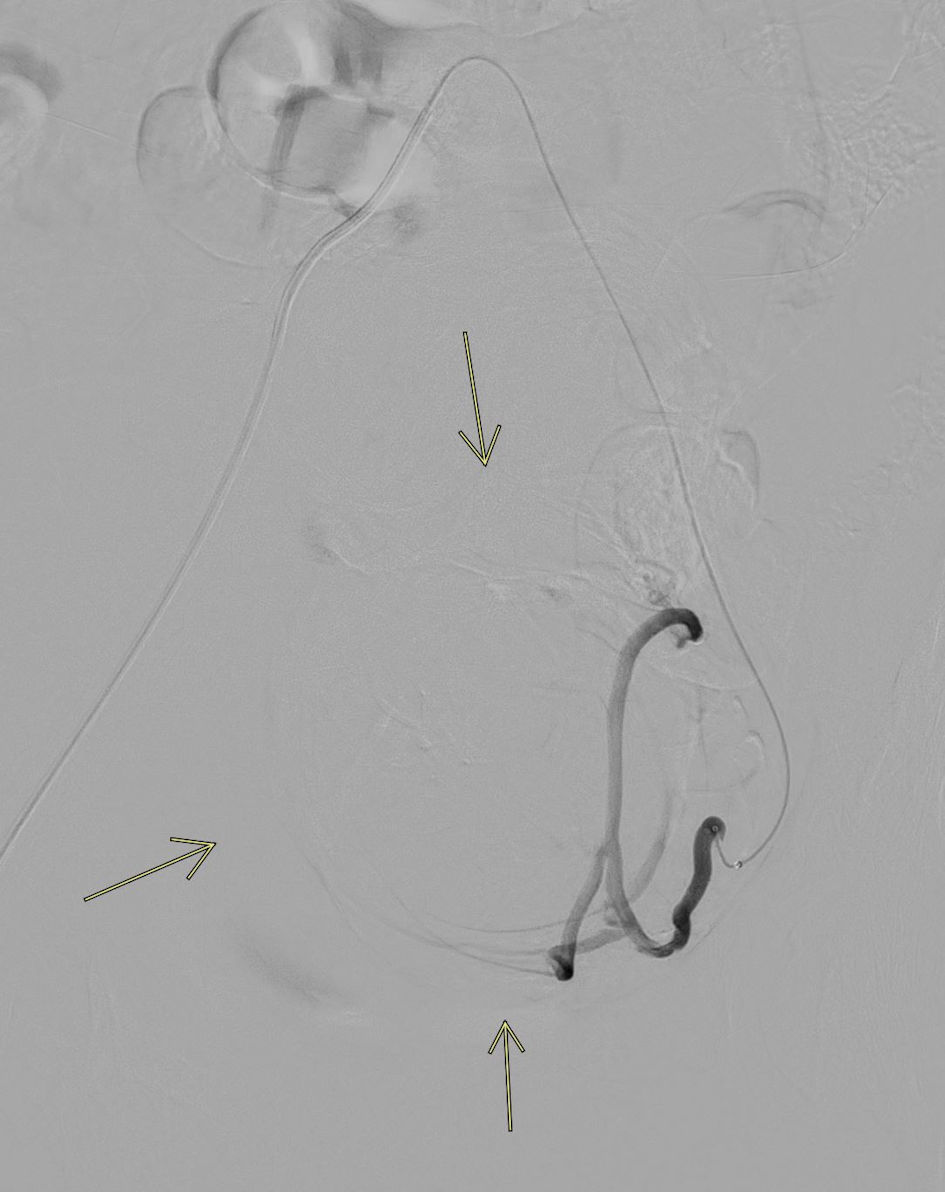

Post-embolization imaging of the left internal iliac artery showed no opacification of intrauterine branches, indicating a successful angiographic result (Fig. 4). The right uterine arteriogram also demonstrated standard anatomy, along with a significant vascular blush consistent with large fibroids. The diagnostic catheter was retracted into the right internal iliac artery, and selective arteriogram was performed. The microcatheter was advanced into the right uterine artery, and intra-arterial embolization was performed by injecting Terumo Hydropearl 200 - 400 µm microspheres. Post-embolization imaging of the right uterine artery showed no opacification of intrauterine branches, confirming successful embolization.

Figure 4. Post-embolization completion angiogram. Left uterine artery angiogram following embolization demonstrates no residual flow to the large fibroids, correlating with excellent radiologic and clinical outcomes (arrows).